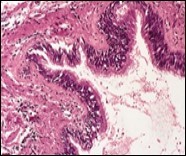

Alternatively, cutaneous ciliated cyst can be lined by non ciliated cuboidal or columnar epithelium with intermingled intercalated, dark or round peg cells. Foci of squamous metaplasia can be occasionally exemplified in the adherent epithelium whereas mucinous cells or apocrine-like features are exceptional 6, 8. Figure 1, Figure 2, Figure 3, Figure 4, Figure 5, Figure 6, Figure 7, Figure 8, Figure 9, Figure 10, Figure 11, Figure 12. 11, 12, 13, 14, 15, 16, 17, 18, 19.

Figure 4.Cutaneous ciliated cyst with a ciliated, pseudostratified columnar epithelium and vascularized fibrous tissue stroma (13).